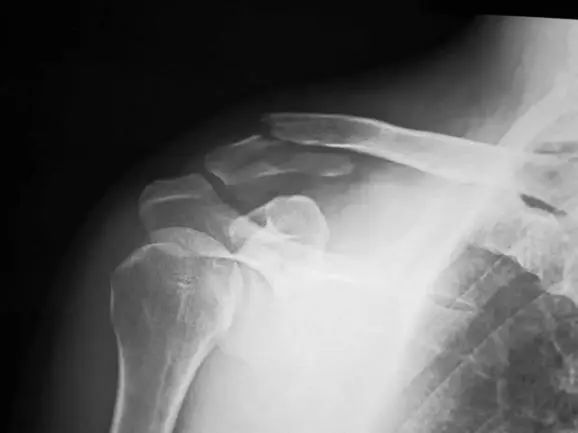

III型為內(nèi)1/3骨折,也分五型:

輕度移位

韌帶斷裂,骨折移位

關(guān)節(jié)內(nèi)骨折

骨骺分離

粉碎骨折